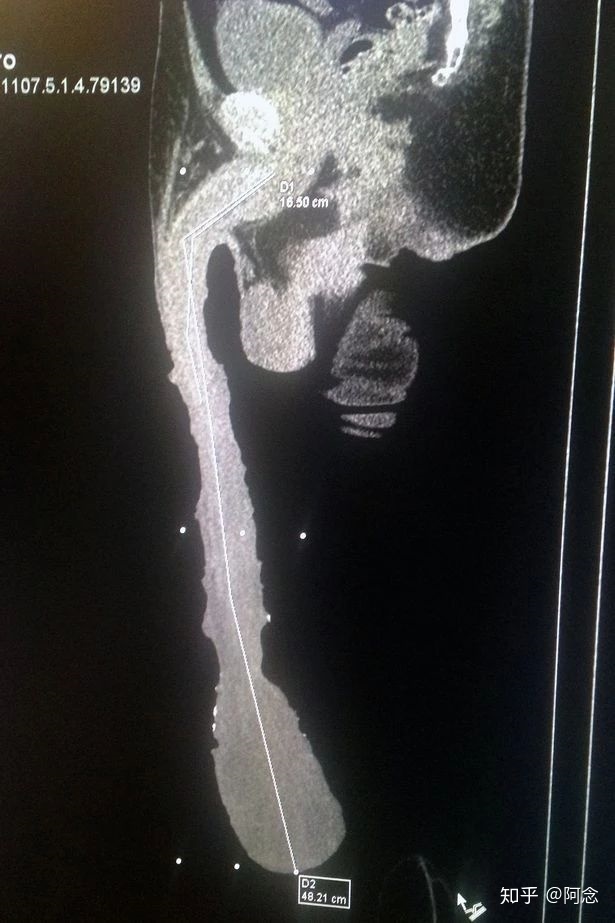

可别以为Jonah Adam的丁丁这么长已经是世界之最了。来自墨西哥的Roberto Esquivel Cabrera,他的丁丁可是达到了48cm。

据Cabrera自己说,是自然长成这样的。他说,9岁时,他就发现自己的丁丁开始不断长大。16岁的时候,尺寸达到了20厘米。到了20岁,长到了接近40厘米。一直到25岁,才停止了继续生长,停在了48厘米

曾为他做过检查的Gonzalez医生却有不同的看法。他认为,这一切的根源还是出在大脑上面,根据扫描结果,Cabrera的大脑右颞叶有一些病变

“很多被外界灌输的意识,比如,女孩子一定得有大胸部,男孩子一定要尺寸长…而Cabrera会因为大脑颞叶的病变而对这些意识变得尤为坚持和执着…于是他从小开始对丁丁长度有了一种蜜汁痴迷,从很小的时候就像非洲的部落一样,开始刻意地改造自己的身体,他改造的方式就是给丁丁绑了一层绑带,增加了丁丁的重量,刻意将它拉长。”